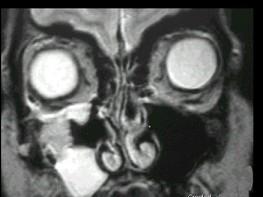

女性,50岁,右鼻塞、脓涕3个月,CT、MRI检查如图所示,请选择正确的答案 ( )

• A.右侧上颌窦积液

• B.右侧上颌窦腺样囊性癌

• C.右侧上颌窦粘膜下囊肿

• D.右侧上颌窦黏液腺瘤

• E.右侧上颌窦黏液囊肿

答案: B